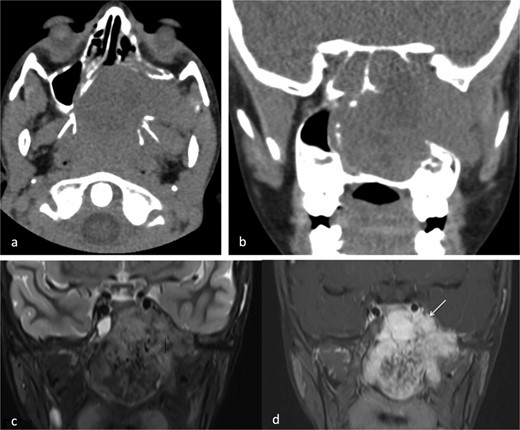

A 9-year-old previously healthy male was referred due to left nasal blockage and mild intermittent epistaxis persisting for 6 months. Nasal endoscopy revealed a clearly evident pinkish mass in the left nasal cavity. Non-contrast Computed Tomography (CT) of the paranasal sinuses (Fig. 1a and b) demonstrated a large, expansile, and ill-defined soft tissue mass with its epicenter in the left nasal cavity and nasopharynx. It extends to the left pterygopalatine fossa and the pterygomaxillary fissure, reaching the masticator space. The mass caused significant bone remodeling and expansion, with some erosions noted at the body and the left greater wing of the sphenoid bone, as well as the medial and lateral pterygoid plates. Additionally, the mass was seen extending to the lateral walls of the maxillary and ethmoid sinuses, bilateral sphenoid sinuses, and the inferior bony orbital wall. Contrast-enhanced Magnetic Resonance Imaging (MRI) showed a predominantly left-sided nasopharyngeal mass measuring 6.9 × 5.9 × 5 cm with increased vascularity (Fig. 1c). The mass replaced the left maxillary antrum, posterior ethmoid air cells, and sphenoid sinuses and invaded the left cavernous sinus (Fig. 1d). A pre-operative left ICA angiogram demonstrated the tumor’s blood supply originating from the vidian artery and inferolateral trunk, with the main supply arising from branches of the left internal maxillary artery (IMA). The vascular branches feeding the tumor from both IMAs were embolized.

(a) Axial non-contrast CT of the paranasal sinuses showing a soft tissue mass obliterating the posterior aspect of the nasal cavity, with extension and remodeling of the left pterygopalatine fossa into the infratemporal fossa. (b) Coronal image demonstrating superior extension into the left sphenoid sinus and left inferior orbital fissure. (c) Coronal T2-weighted MRI showing a large JNA with heterogeneous signal intensity and multiple flow voids consistent with hypervascularity. (d) Post-contrast coronal T1-weighted MRI demonstrating avid contrast enhancement and invasion of the left Meckel’s cave and cavernous sinus (arrow).